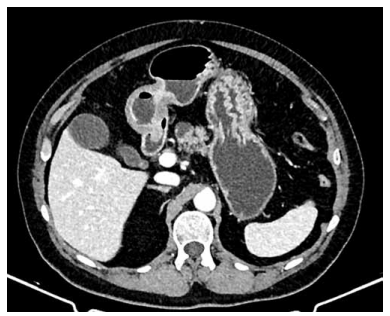

Paciente do sexo feminino, de 62 anos, é diagnosticada

com carcinoma ductal invasivo de mama esquerda. Durante o estadiamento, realiza tomografia computadorizada de abdome, que identifica cisto pancreático na cabeça

do pâncreas, sugestivo de neoplasia mucinosa papilar

intraductal (IPMN), conforme imagem a seguir:

(Arquivo pessoal; imagem usada com autorização)

De acordo com os critérios de Fukuoka (2017) revisados, qual das seguintes características é considerada um “critério de alto estigma” que indica necessidade de ressecção cirúrgica?